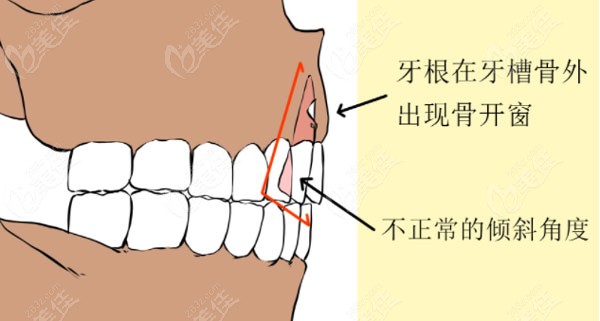

骨开窗示意图

正畸形成骨开窗和骨开裂有啥区别?看骨开窗示意图自行判断

骨开窗,骨开裂示意图

正畸形成骨开窗和骨开裂有啥区别?看骨开窗示意图自行判断